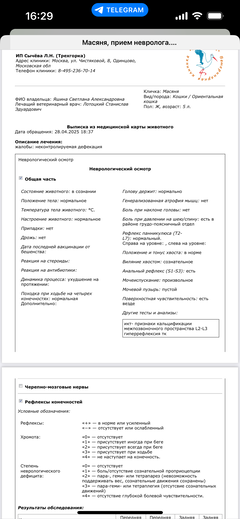

Забрали. Оказалось, что у малышки постоянно болит спина...

Ярко выраженная болезненность в области крестца, на обезболе полегче. По результатам приема невролога проведена миелография - множественная компрессия, возможно опухоль, возможно грыжа, нужно удалять...